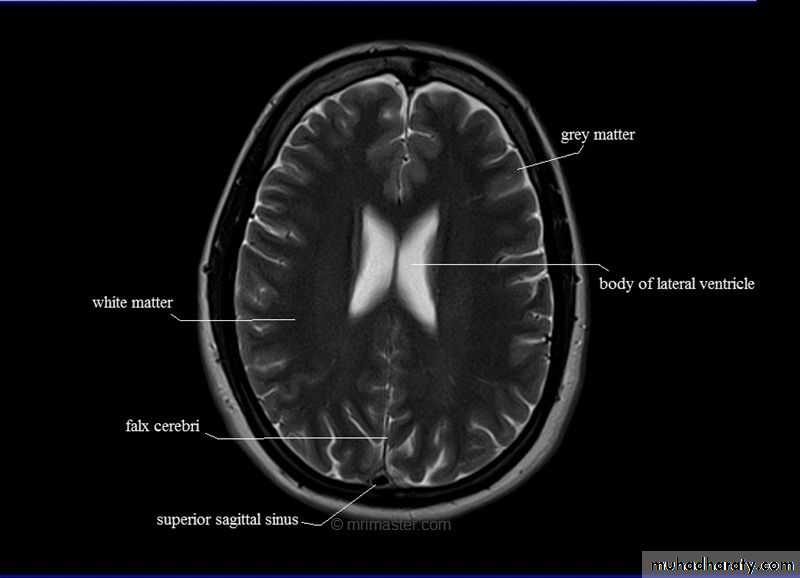

The lateral ventricles

• Situated in the cerebral hemispheres, it has a• body, an anterior horn in the frontal pole, posterior

• horn in the occipital pole & inferior horn in the

• temporal pole.

• The two lateral ventricles are interconnected by

• interventricular foramen and it also communicates

• with the 3rd ventricle.

• All ventricles are lined by ependyma.

Ventricles

Lateral

Third

Fourth